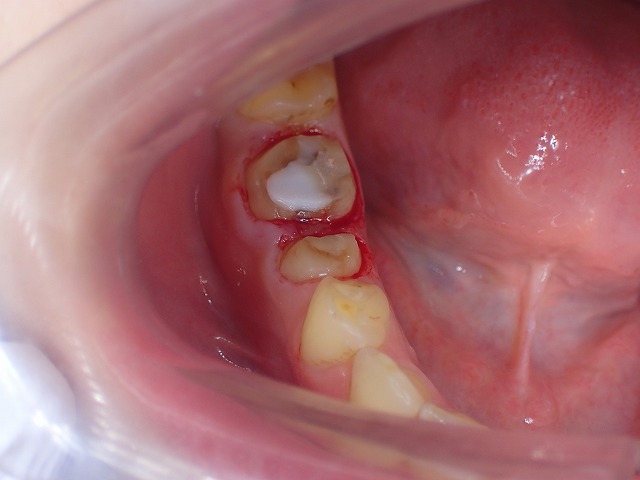

左側のcad/cam冠をジルコニアクラウンに交換

激しい歯ぎしりでCAD/CAM冠が

大きく摩耗しています。

そのため歯と歯の間に隙間ができています。

ジルコニアクラウンに交換

左側のCAD/CAM冠を除去してジルコニアを制作

cad/cam冠などのプラスチック関係の

かぶせ物は、歯肉に炎症を起こす場合がほとんどです。